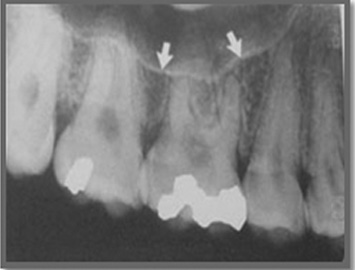

Roots of upper teeth are sometimes very close to the maxillary sinus floor

Some times the root of the upper teeth may be in close vicinity or within the maxillary sinus and during the procedure of extraction a communication may occur between the oral cavity and the antral environment. This leads to passage of liquid through the oral cavity into the sinus and discharge through the nose. This may heal by itself or can be managed efficiently by the oral surgeon.